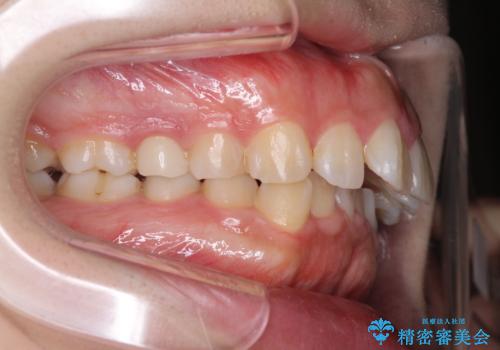

がたがたと出っ歯を直したい ワイヤーによる抜歯矯正

- ガタガタと出っ歯を主訴に来院されました。

上下左右の歯を1本ずつ、合計4本抜歯してワイヤーにて矯正治療をすることとなりました。

前から4番目の歯を抜歯することが多いのですが、右上の前から5番目の歯が神経の治療済みであり、こちらの歯を抜歯する計画としました。

通常より治療期間を要しましたが、健康な歯を残すことができました。